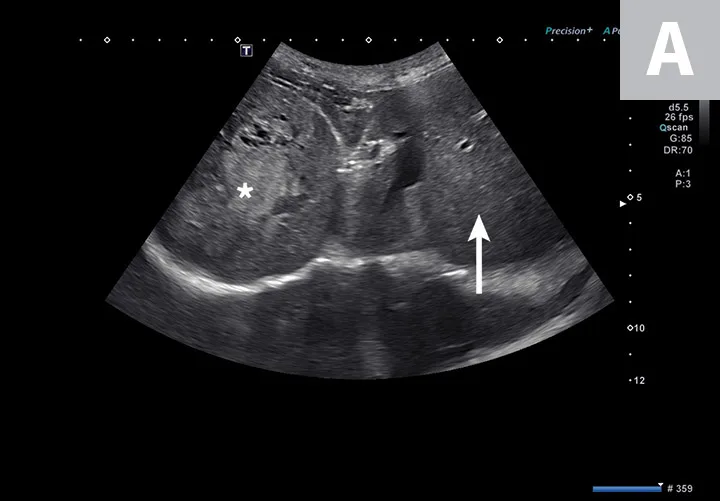

1. Urinary Bladder Evaluation & Cystocentesis

Cystocentesis allows sterile collection of urine while avoiding the potential complications of manual bladder compression, urethral catheterization, or contamination from free-flow collection.4 Ultrasound guidance can help decrease risk of unintentionally inserting the needle into nearby structures (eg, colon, caudal vena cava, descending aorta) and allows for brief assessment of the urinary bladder. Although some pathologic changes in the urinary bladder (eg, mild cystitis) can be subtle and easily overlooked, other diseases can be very apparent. Cystic calculi can range in shape and size but, when large enough, may have a hyperechoic interface that causes a distal acoustic shadow (Figure 1). In patients with hematuria, blood clots with different shapes can float in the urine or rest dependently against the bladder wall. Neoplasia of the urinary bladder can differ in visualized size and echogenicity; however, neoplasia typically originates from the bladder wall, demonstrates irregular margins, and protrudes into the bladder lumen. If a mass is identified in the urinary bladder, cystocentesis is not recommended to prevent potential seeding of neoplastic cells in the soft tissue along the path of the needle.

FIGURE 1

Sagittal image of the urinary bladder (UB; cranial aspect toward the left side of the image). Numerous calculi (between calipers) are present along the dependent aspect of the urinary bladder (away from the probe with the patient in dorsal recumbency) and, unlike in cases of neoplasia, are hyperechoic and cast a clean acoustic shadow.